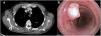

A 66 year-old male with a history of smoking (35 pack-year units) and gastric adenocarcinoma was referred to a Pulmonology consultation because of abnormal imaging findings. During routine follow-up, thoraco-abdominal computorized tomography was performed, revealing a polypoid lesion in the middle third of the trachea, with a maximum diameter of 12mm (Fig. 1A). He was asymptomatic and had a normal physical examination. Flexible bronchoscopy was performed, confirming the presence of an intra-luminal, highly vascularized polypoid lesion in the middle third of the trachea (Fig. 1B). Biopsies were performed, providing the diagnosis of a pleomorphic adenoma. After multidisciplinary discussion the patient was referred to Thoracic Surgery; segmental tracheal resection was successfully performed.

(A) Thoracic computorized tomography in axial plane demonstrating a polypoid lesion in the left side of the middle third of the trachea, with a maximum diameter of 12mm. (B) Endotracheal view of the trachea, confirming the presence of a vascularized polypoid lesion in the left wall of the middle third of the trachea.